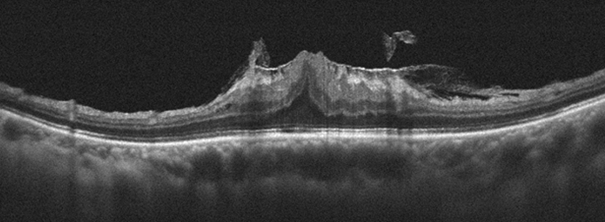

(圖二)共軛光掃描儀檢查可檢查出不同型態的黃斑部皺褶分期。隨著疾病的進展,黃斑部也產生結構的破壞。

(圖四)共軛光掃描儀檢查發現左眼黃斑部皺褶已導致黃斑部結構嚴重變形。